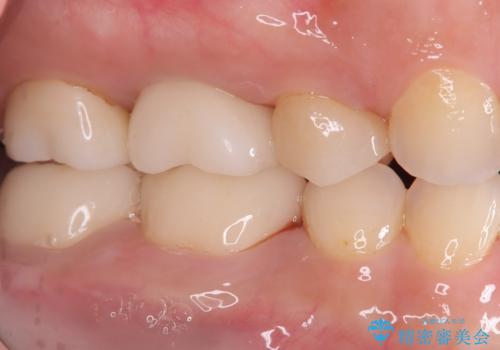

- 右上の6番の奥歯の痛みを主訴に来院されました。精密検査の結果、根管内を歯科用顕微鏡で確認したところ、肉眼では見えないクラック(ひび割れ)が発見されました。このクラックが痛みの原因であり、将来的に歯の保存が難しいと判断。患者様と話し合い、歯を残すことを諦め、抜歯と同時にインプラントを埋入する抜歯即時埋入インプラントによる治療計画を立案しました。これにより、治療期間と身体への負担を最小限に抑え、確実な解決を目指しました。

今回の治療では、まず原因となっていた奥歯を慎重に抜歯し、その直後にインプラントを埋入しました。この抜歯即時埋入により、抜歯からインプラント埋入までの期間を省き、骨の吸収を最小限に抑えられました。治療後は痛みや腫れも少なく、患者様は快適に過ごしていただけました。最終的に、わずか3ヶ月でセラミッククラウンを装着。機能性と審美性を兼ね備えた新しい歯により、長年の痛みが解消され、快適な食生活を取り戻していただけました。